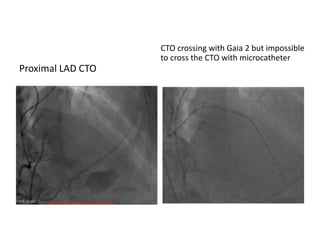

Proximal LAD CTO

CTO crossing with Gaia 2 but impossible

to cross the CTO with microcatheter